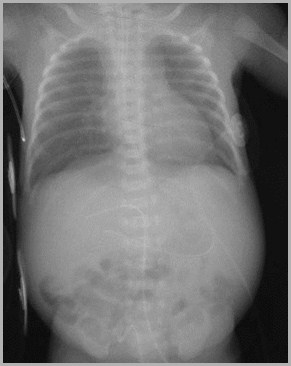

UAC too high at T4Umbilical Venous Catheter passes thru foramen ovale into left atrium andleft pulmonary vein

4